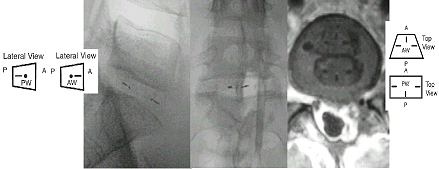

Posición adecuada del implante PDN

Las flechas dentro del hidrogel indican la posición del implante